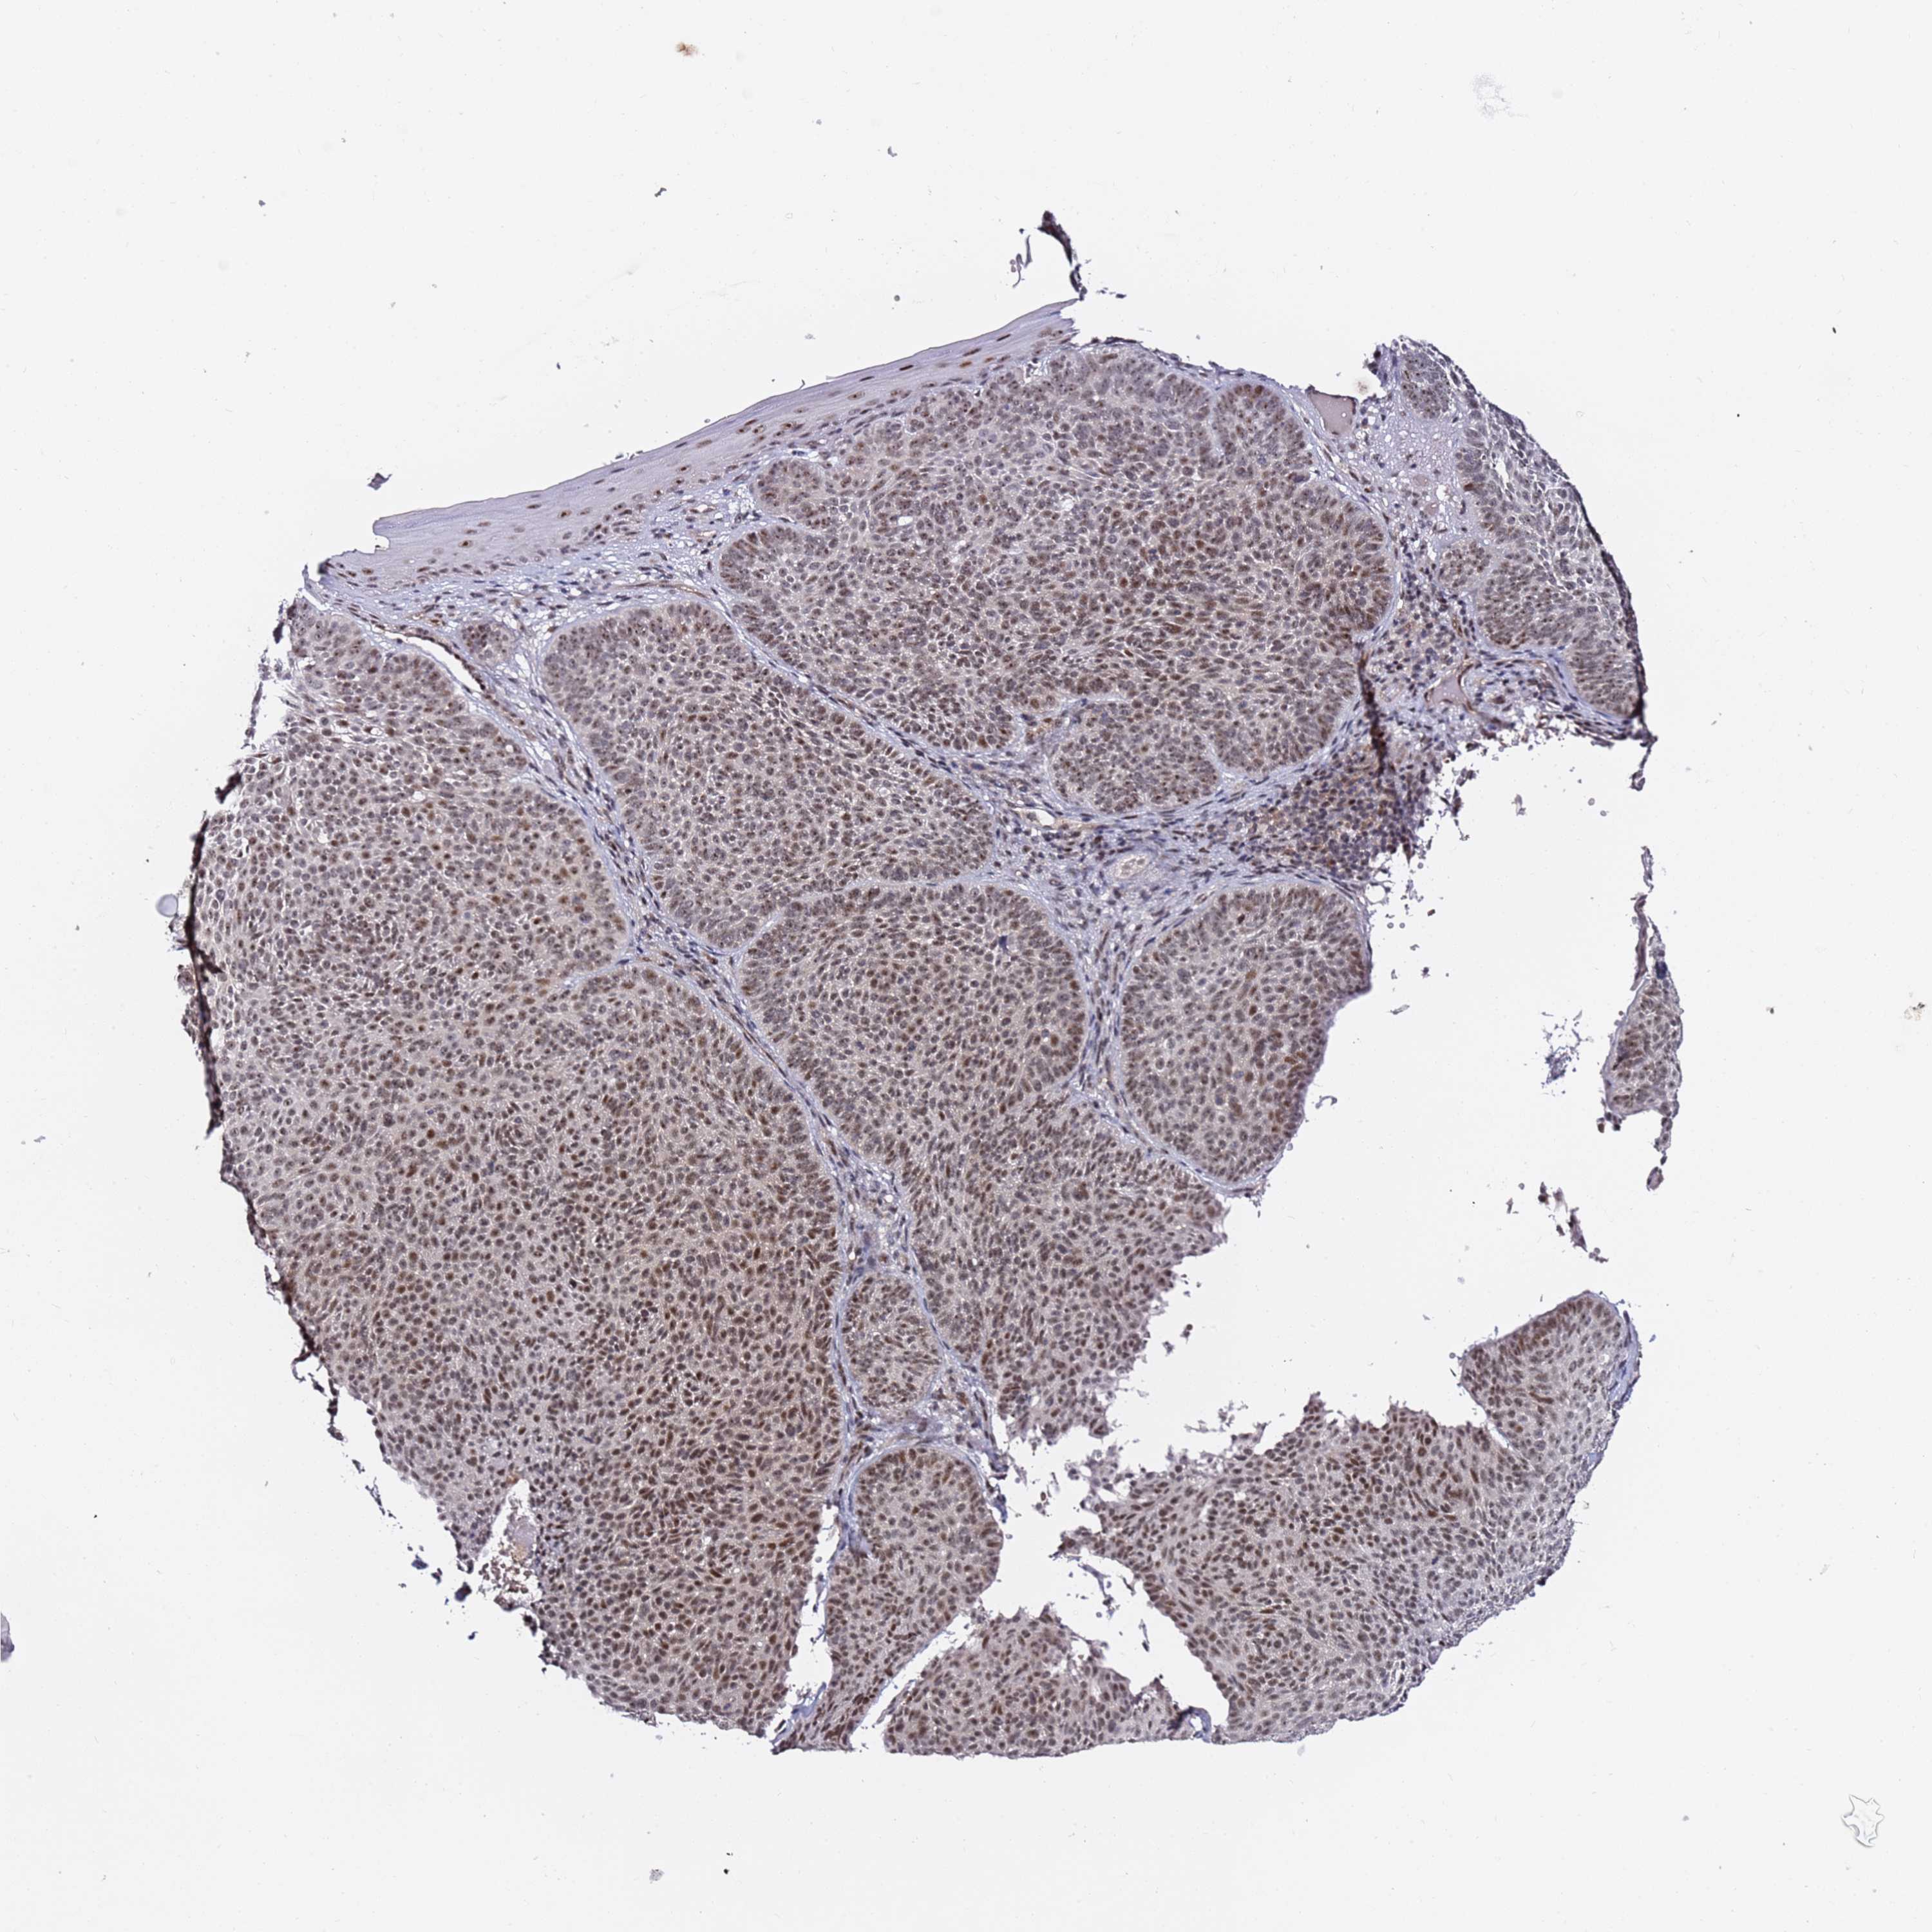

SKIN CANCER - Protein expressioni

A mouse-over function shows sample information and annotation data. Click on an image to view it in a full screen mode. Samples can be filtered based on level of antibody staining by selecting one or several of the following categories: high, medium, low and not detected. The assay and annotation is described here.

Each image is clickable and will lead to virtual microscopy that enables deeper exploration of all samples and also displays staining intensity scores, fraction scores and subcellular localization as well as patient and tissue information for each sample.

Antibody HPA046681

Staining

High

Intensity

Strong

Quantity

>75%

Location

Nuclear

Basal cell carcinoma